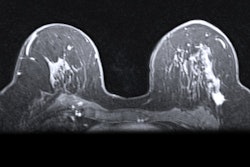

The researchers set the time between initial screening mammogram and MRI exams at two months to reduce interval cancers. The women underwent a sub-10-minute MRI protocol, with readers having more than 15 years of experience.

The study included data collected from 200 women with breast densities categorized as ACR C or D, indicating heterogeneously and extremely dense breasts, respectively.

Image-guided biopsy revealed four cancers, three of which were deemed invasive in women presenting with category C breast density. The other one cancer case was a non-calcifying ductal carcinoma in situ (DCIS) in a woman with category D breast density. This resulted in a cancer detection rate of 20 per 1,000, a positive predictive value (PPV) of recall of 50%, and a PPV of biopsy of 62.5%.